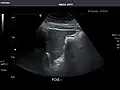

Ultrasonography of the liver with some standard measurements[6]

In patients with deranged liver function tests, ultrasound may show increased liver size (hepatomegaly), increased reflectiveness (which might, for example, indicate cholestasis), gallbladder or bile duct diseases, or a tumor in the liver.

Ultrasonography of liver tumors involves two stages: detection and characterization. Tumor detection is based on the performance of the method and should include morphometric information (three axes dimensions, volume) and topographic information (number, location specifying liver segment and lobe/lobes). The specification of these data is important for staging liver tumors and prognosis. Tumor characterization is a complex process based on a sum of criteria leading towards tumor nature definition. Often, other diagnostic procedures, especially interventional ones, are no longer necessary. Tumor characterization using the ultrasound method will be based on the following elements: consistency (solid, liquid, mixed), echogenicity, structure appearance (homogeneous or heterogeneous), delineation from adjacent liver parenchyma (capsular, imprecise), elasticity, posterior acoustic enhancement effect, the relation with neighboring organs or structures (displacement, invasion), vasculature (presence and characteristics on Doppler ultrasonography and contrast-enhanced ultrasound (CEUS).